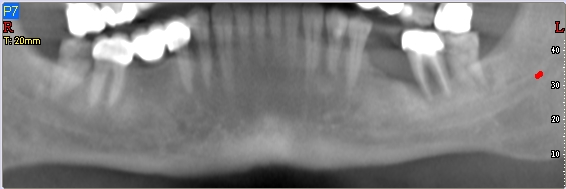

- Η ακτινογραφική εικόνα εξαρτάται από τον βαθμό της διήθησης. Η Υπολογιστική τομογραφία είναι άκρως απαραίτητη για τον ακριβή προσδιορισμό της οστικής καταστροφής.

- Ακτινογραφικά παρατηρείται διαυγαστική οστεολυτική αλλοίωση με ασαφή και ακανόνιστα όρια η οποία ξεκινά σαν περιφερική οστική διάβρωση.